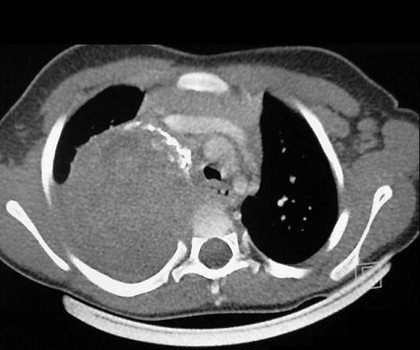

Далее определяют визуально наличие опухоли с помощью рентгенографии, компьютерной томографии, МРТ, ультразвукового исследования.

Диагностика с помощью МРТ дает более точную картину опухоли.

нейробластома на диагностическом снимке

- Рентгенографию грудной клетки, которая сможет отыскать локализованную там опухоль;

- КТ, МРТ и другие методы.

Подозрение на отдаленное метастазирование ставит задачу немедленного и особо тщательного изучения не только костного мозга, но и костей скелета. С данной целью использую такие методы, как R-графия, радиоизотопная сцинтиграфия, трепано- и аспирационная биопсия, КТ и МРТ.